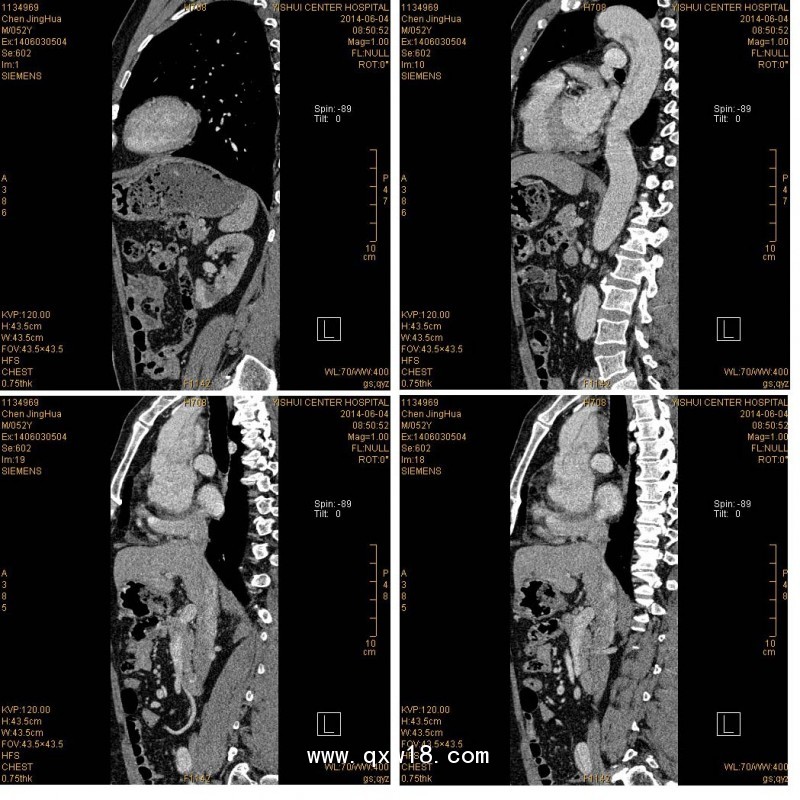

醫(yī)用膠片用于承載醫(yī)療影像圖文信息的介質。包括各種超聲、三維重建、病理、彩色膠片照相、CR、DR、MRI、牙片、眼科影像、紅外乳腺、陰道鏡等各類醫(yī)學影像、圖文報告。